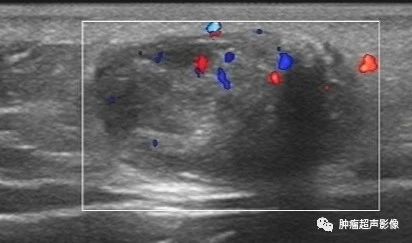

5,面部可移动无痛性肿块,皮肤真皮与皮下脂肪层交界处见低回声,边界清,内见粗大钙化,内见丰富动脉血流,符合典型毛母质瘤的特点。